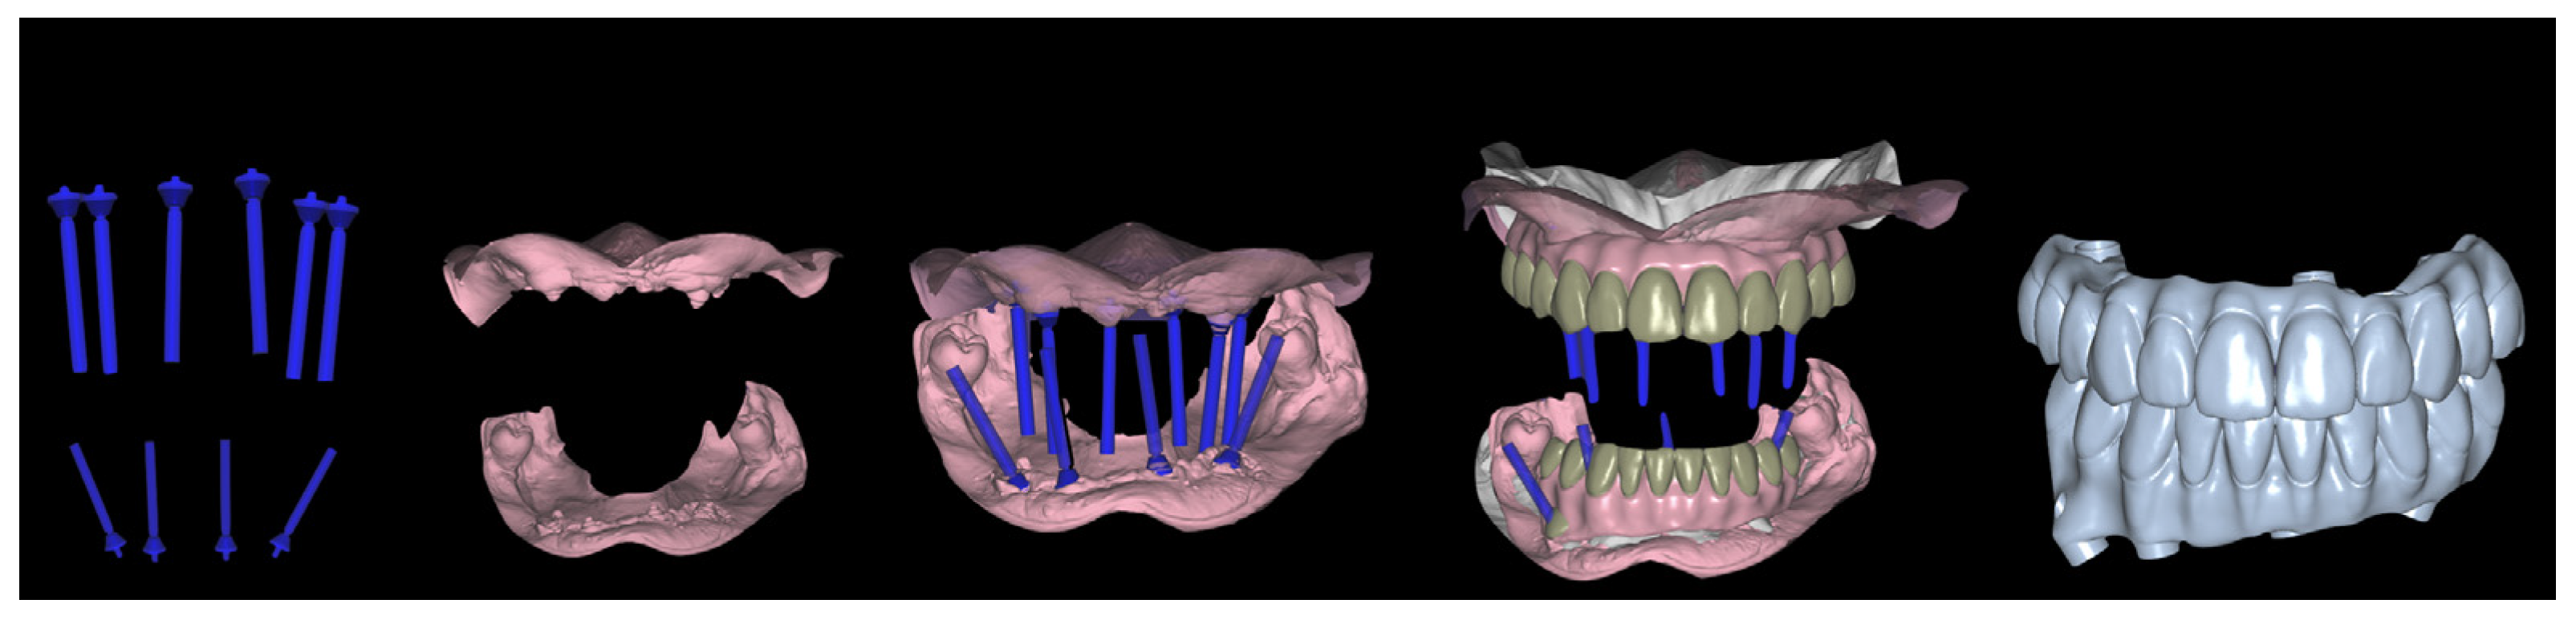

2. Material and Methods